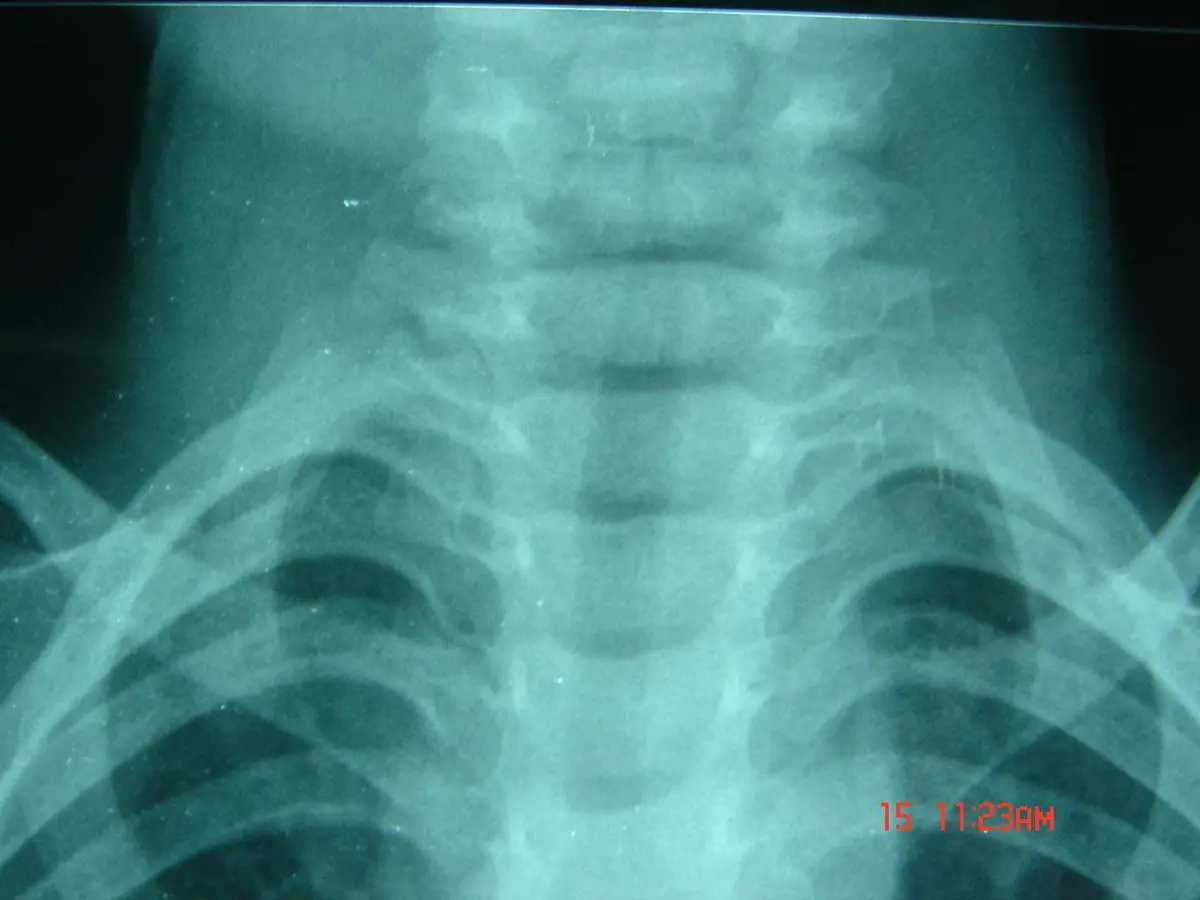

本題影像與前題相同,為同一病患的頸胸部正面 X 光(AP view)。影像顯示聲門下氣管對稱性收窄,形成典型的「鐘樓徵(steeple sign)」,兩側肺野清晰,確認為哮吼(病毒性喉氣管炎)的放射線學表現。此影像為承上題的連結,再次強調本病例為病毒性上呼吸道感染。